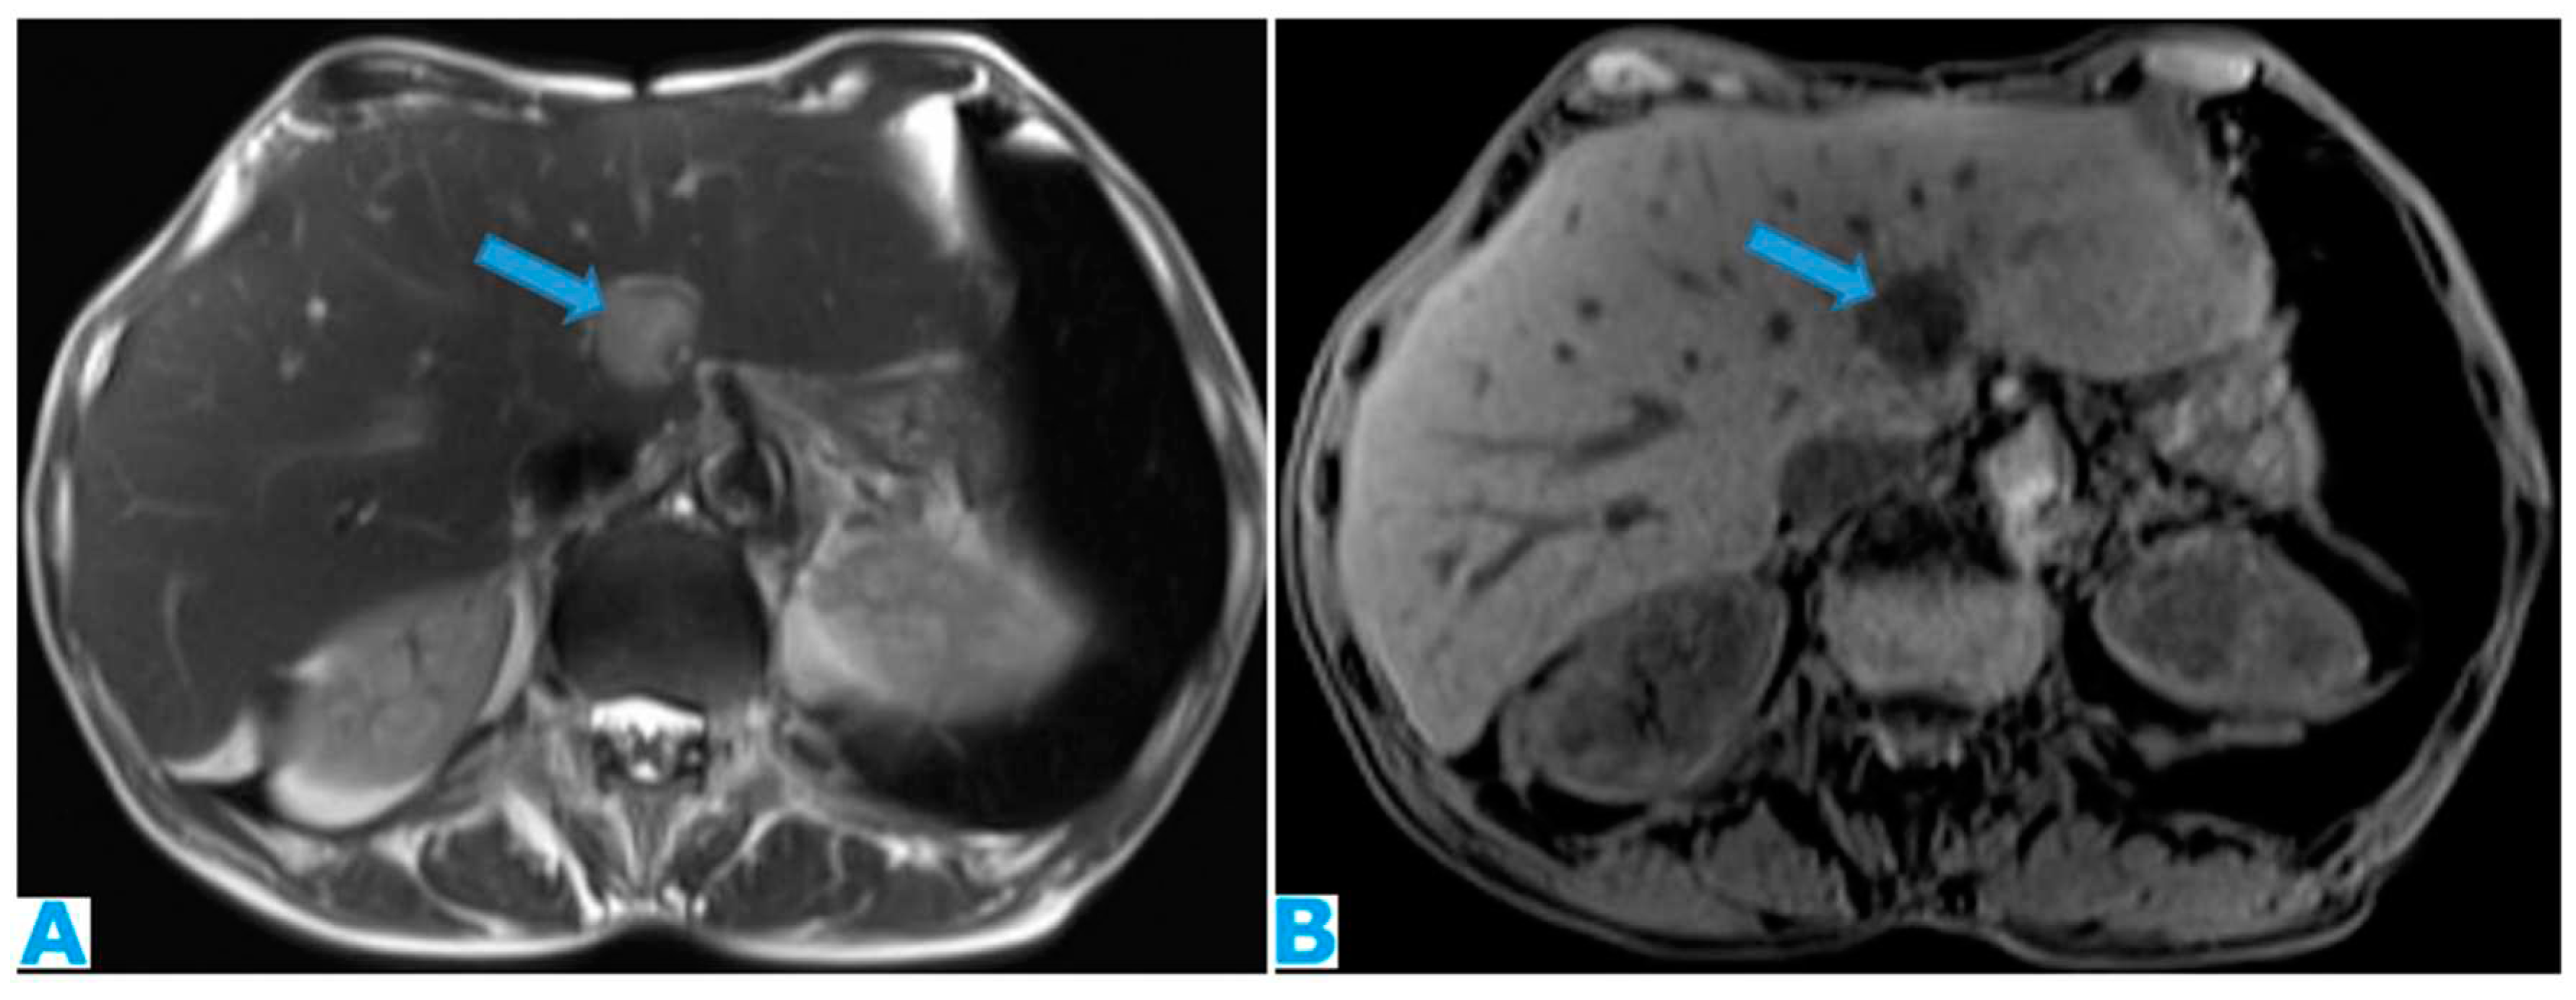

Figure 38.

Axial T2WI (A). PC from ovarian adenocarcinoma : Loculated ascites within the mesentery (*). Axial CE-CT (B). PC from breast carcinoma: Concomitant ascites within greater (arrow) and lesser (*) sacs.